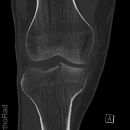

Kniegelenk

Tibiakopf